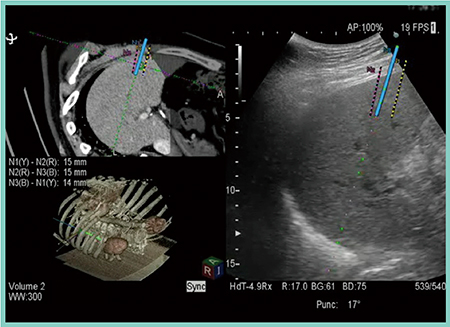

3D Sim-Navigatorを用いたT30でのRFAシミュレーションの基本的な流れは次の通りである。まず,1本目の穿刺ラインに沿って仮想針を設定すると電極針の絶縁体と針先を示す2つの×印が表示される。2本目,3本目も同様に仮想針を設定するが,この時,3本の針先を二等辺三角形の頂点となるようC-plane画像を見ながら配置すると,きわめて均等な針間距離が得られる。同時に針間距離も表示され,ドジメトリテーブルに沿った間隔になっているかどうかが確認できる(図2)。

図2 3D Sim-Navigatorを用いたRFAシミュレーション(3本目の穿刺)

図3 実証試技における北半球の1本目の穿刺

図4 実証試技における北半球の平行穿刺